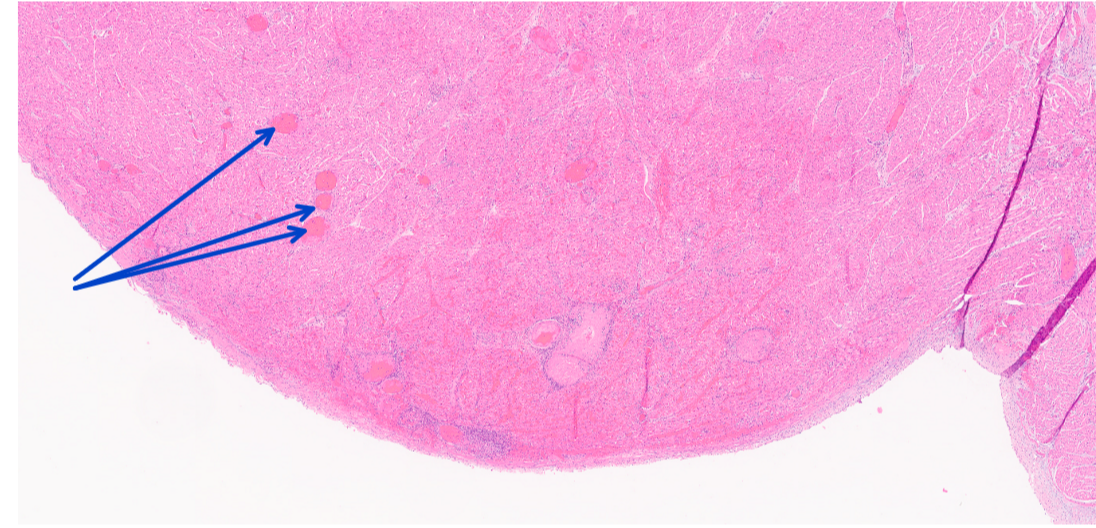

What would the morphologic diagnosis for this lesion?

acute purulent glomerulonephritis with bacterial colonies

Identify this structure:

bacterial colonies

Q

congestion

fibinous thrombosis

bacterial septic emboli